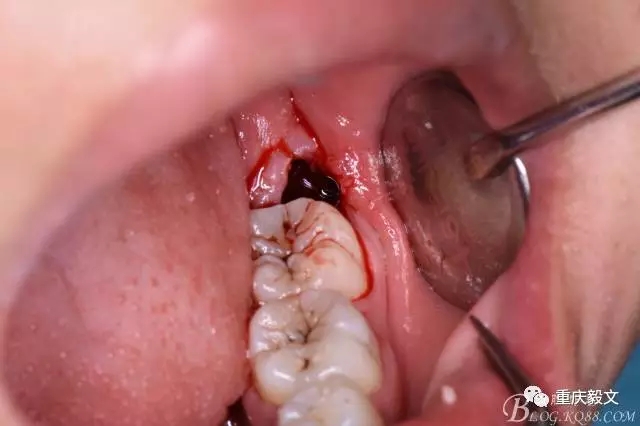

圖13.梃子放在頰側(cè)、挺松牙根

圖14.38牙根即將脫出牙槽窩

圖15.牙根脫位受阻,遂將牙根分為兩根

圖16.取出38遠(yuǎn)中根

圖17.然后取出38近中根

圖18.牙槽窩完整、無(wú)擴(kuò)大、無(wú)撕裂